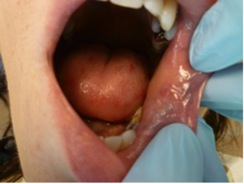

The patient presented with a raised, round, circumscribed lesion on the left buccal mucosa (Figure 6). The lesion was 8 mm in diameter and not ulcerated. The patient stated that the lesion had been present for about 5 years and was slowly increasing in size. The patient requested that it be removed.

Fig 6. The patient presented with a raised, round, circumscribed lesion on the left buccal mucosa. The lesion was 8 mm in diameter and not ulcerated.